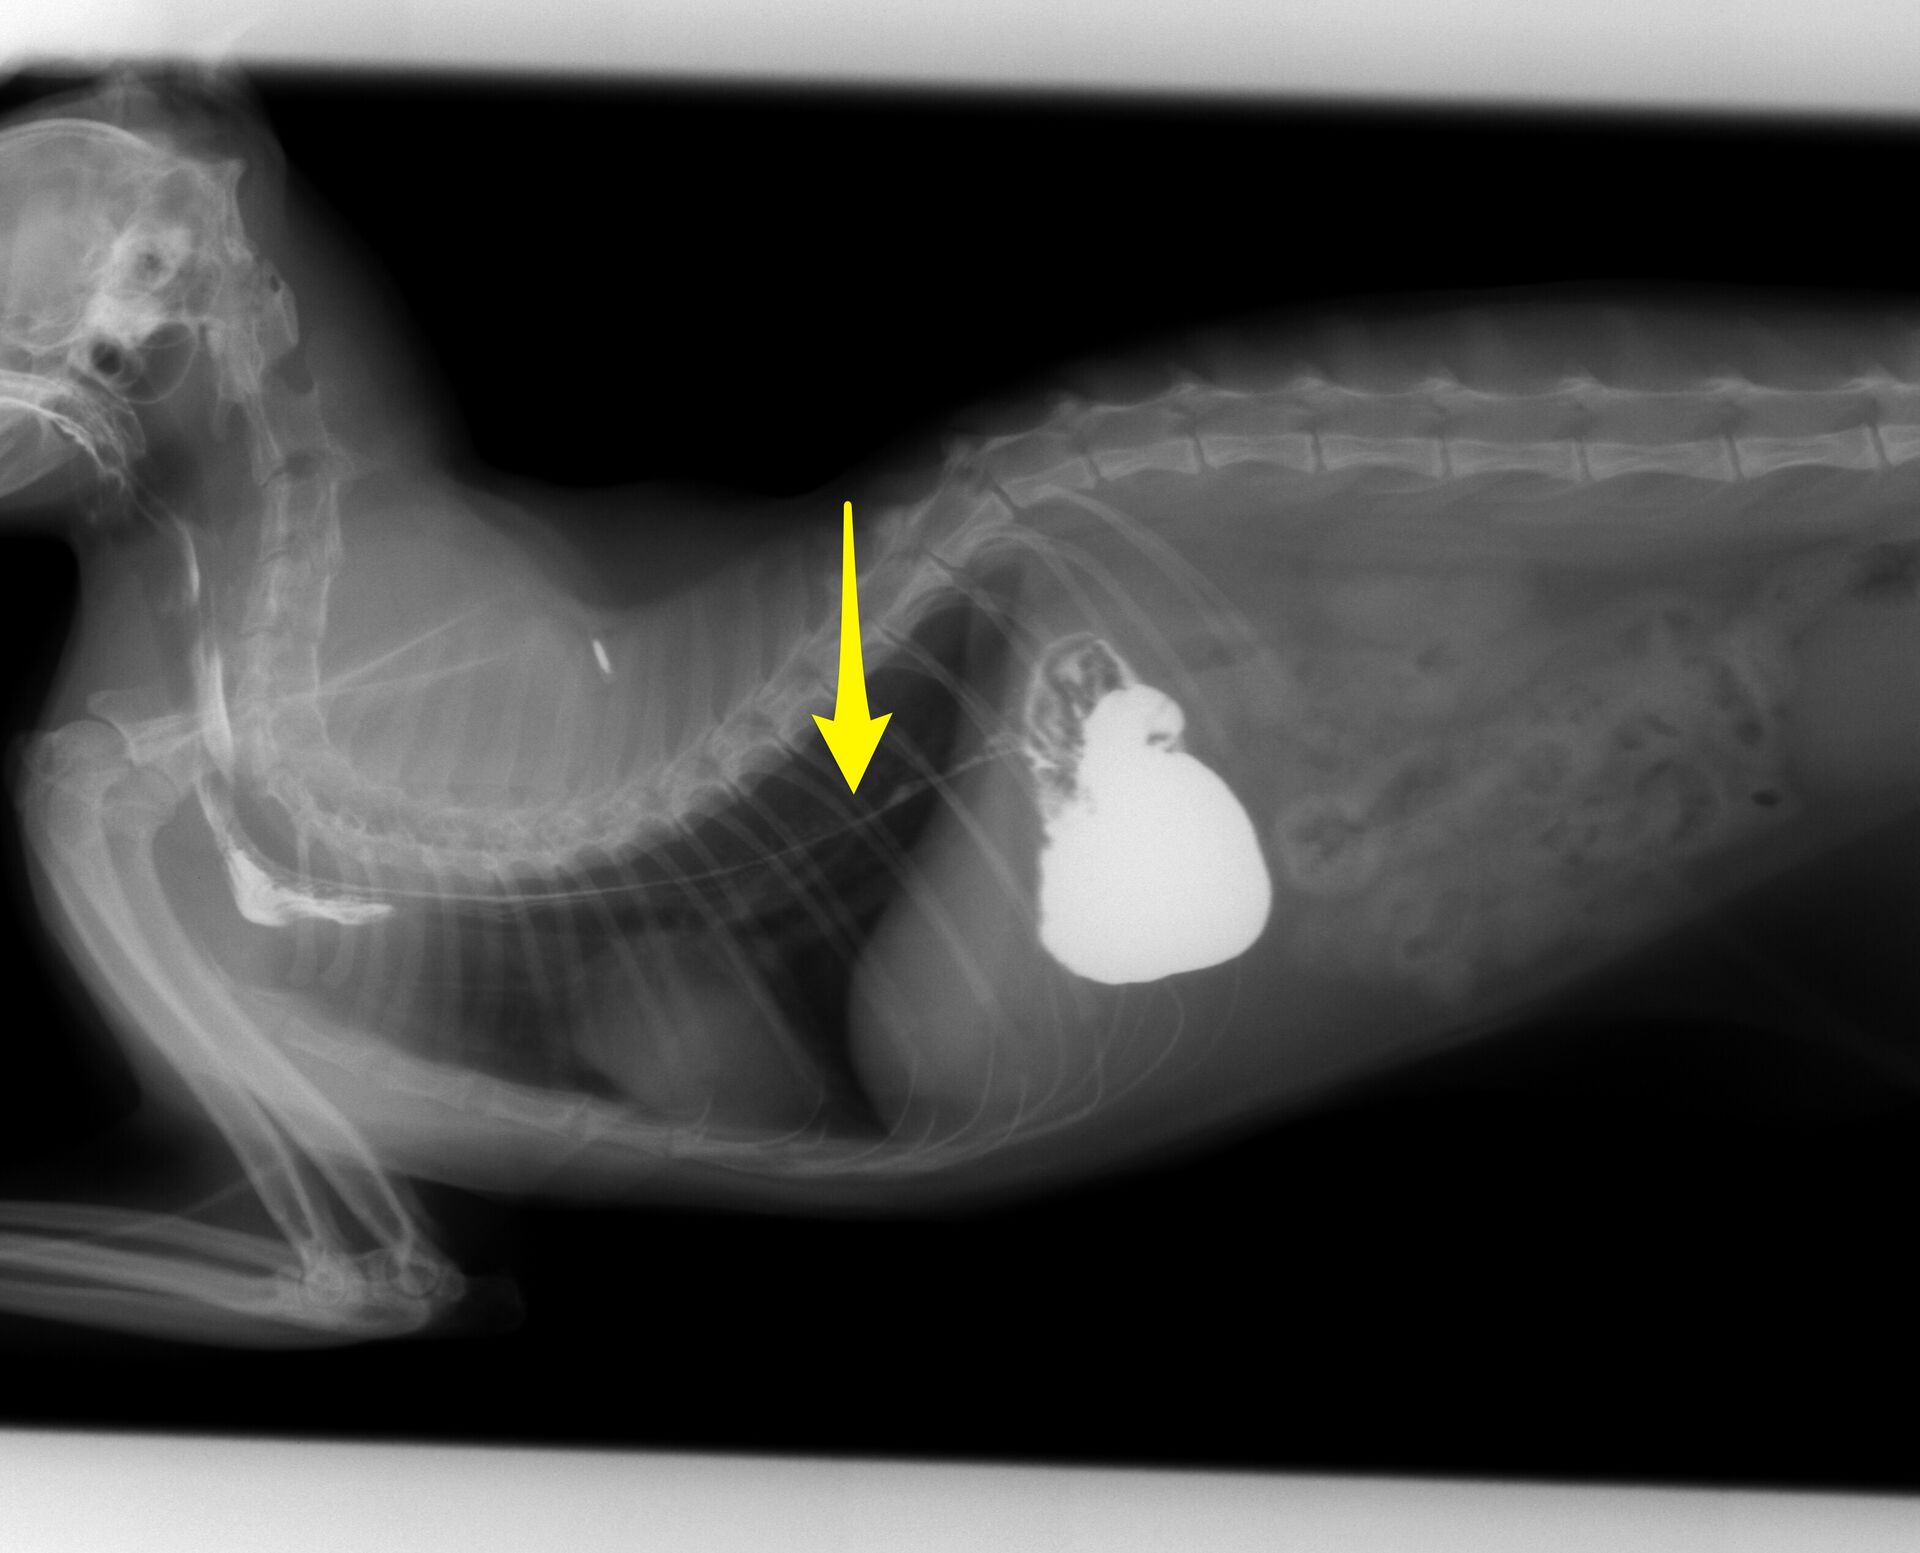

こうなってしまうと、開腹して腸を切開し紐を切断しながら取り除くしかありません。実際、診察のその日の夜に緊急手術することになりました。その様子が下の写真です。

手術前に奥歯に絡まっていた紐を外しました。この紐は食道に続いていました。

小腸内に紐状異物があるため腸が寄りアコーディオン状になっています。1箇所だけを切開して引っ張り出すといいように思いますが、抵抗が強すぎて無理に引っ張ると腸が裂けてしまいます。今回の場合は胃を1箇所、腸を4箇所切開し、紐を取り除きました。

かなり大変な手術になってしまいました。一番下の写真が取り出した紐です。手術後は徐々に食欲が回復し、3日後には退院できました。